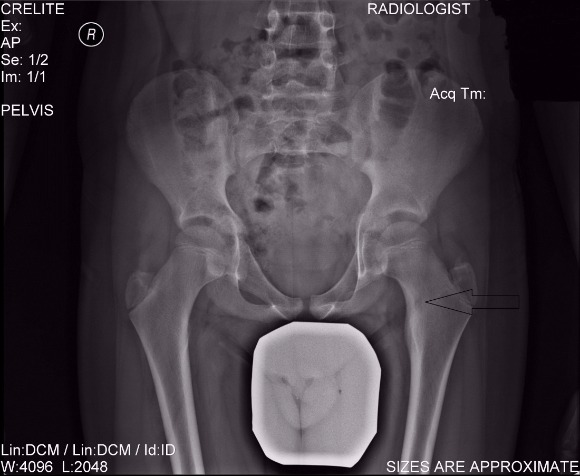

The x-ray shows an osteoid osteoma in the upper femur, which was treated by Dr. Zenios using radiofrequency cauterization.